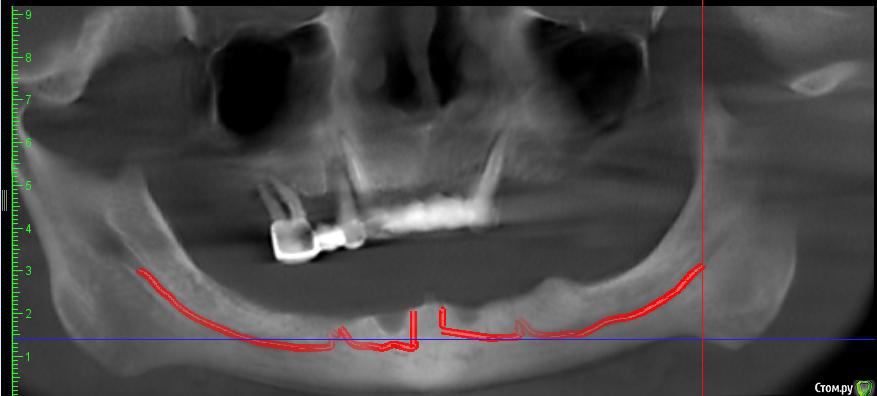

Romanson Опубликовано 29 июня, 2017 Поделиться Опубликовано 29 июня, 2017 (изменено) Здравствуйте, уважаемые коллеги.Помогите определить правильную тактику по данному случаю.Сильный недостаток костной ткани. И необычная анатомия нижнечелюстного канала, ощущение что ветки выходят за пределы ментального отверстия, могу ли я игнорировать всё, что за пределами ментального отверстия для установки 4х имплантатов для протезирования условно съемным протезом? https://www.youtube.com/watch?v=GZecWBkPz2w Если нужно я загружу КТ. Изменено 29 июня, 2017 пользователем Romanson Ссылка на комментарий

kriokov Опубликовано 29 июня, 2017 Поделиться Опубликовано 29 июня, 2017 вкрутил бы четыре. Из неприятностей -- самое паршивое не снижение или потеря чувствительности во фронте альвеолярного (здесь это не страшно, тк думаю слизистая губы и кожа иннервируются ветками после выхода нерва из ментального) , а возможность неврита. Тогда придется болты выкручивать. Попробуйте с направлением сверления подумать на кт. Ссылка на комментарий

АнтонТЛТ Опубликовано 30 июня, 2017 Поделиться Опубликовано 30 июня, 2017 Такие ветки есть всегда, что-то же должно иннервировать фронтальную группу зубов))По тактике, ставить 4 в подбородок Ссылка на комментарий

Bier Опубликовано 30 июня, 2017 Поделиться Опубликовано 30 июня, 2017 а у меня вот были осложнения. Ставить туда шурупы не рекомендовано. Я бы обходил это образование. Ссылка на комментарий

Bier Опубликовано 1 июля, 2017 Поделиться Опубликовано 1 июля, 2017 кровотечение - это если там просто сосуд, как чаще всего и бывает, по этому и проходит без последствий. Но может быть и серьезный болевой синдром. Ссылка на комментарий